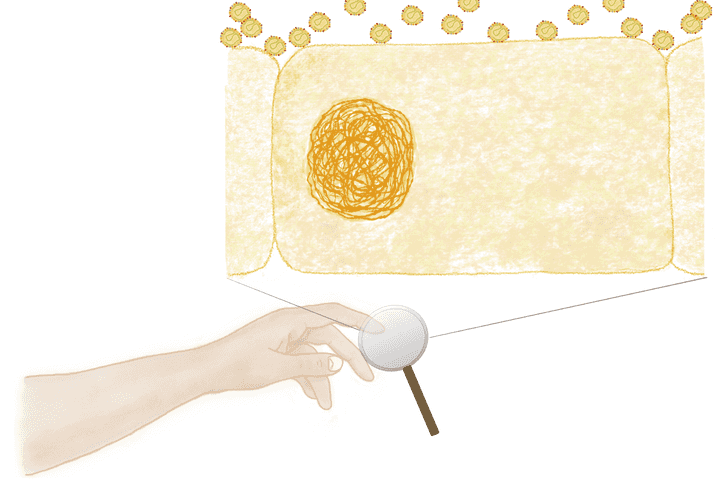

coronavirus particles settling on the cells of the skin. © Sunaina Rao.

An infected COVID 19 individual, releases thousands of virus-containing droplets each time he/she coughs or sneezes. Each droplet harbours millions of coronavirus particles. These particles once in the air, will eventually settle on the nearest surface. On touching this surface, the viruses latch onto your hand, and from here they readily hitch a ride into your nasal tract, where an active infection can begin. So, what’s of utmost importance is to not only wash away these viruses as soon as possible, but also destroy them in the process.